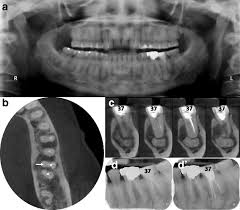

Difficulties In The Diagnosis Of Periapical Translucencies And In The Classification Of Cemento Osseous Dysplasia Bmc Oral Health Full Text

Difficulties In The Diagnosis Of Periapical Translucencies And In The Classification Of Cemento Osseous Dysplasia Bmc Oral Health Full Text from media.springernature.com